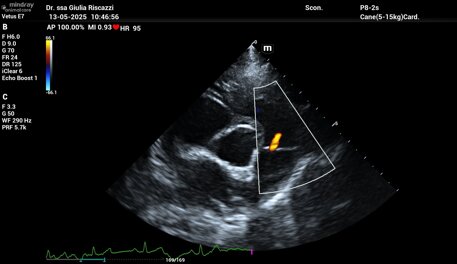

Il paziente viene posizionato in decubito laterale con l’ausilio di appositi tavoli imbottiti per rendere l’accertamento il più possibile confortevole per i nostri pazienti. Con sonde ecografiche appropriate l’ecocardiografia valuta sia la morfologia del cuore, delle valvole e dei grossi vasi come aorta ed arteria polmonare, sia la sua contrattilità e funzione. Il color Doppler usato nell’ambito dello stesso esame ecocardiografico ci permette invece di studiare i flussi di sangue all’interno delle camere cardiache e di stimare le loro velocità e movimenti.